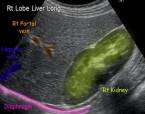

УЗИ печени – это недорогая и доступная диагностика.

Это великолепный способ проверить печень на заболевания желчных протоков, желчного пузыря, а также оценить сосудистое состояние.

Ультразвуковое исследование также способно оценить следующие показатели:

- Размер печени.

- Капсульный контур (гладкий, грубый, дольчатый).

- Паренхиматозная эхогенность.

- Наличие и проходимость кровеносных сосудов.

- Желчное дерево.